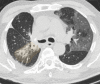

The coronavirus disease 2019 (COVID-19) pandemic is a global health care emergency. Although reverse-transcription polymerase chain reaction testing is the reference standard method to identify patients with COVID-19 infection, chest radiography and CT play a vital role in the detection and management of these patients. Prediction models for COVID-19 imaging are rapidly being developed to support medical decision making. However, inadequate availability of a diverse annotated data set has limited the performance and generalizability of existing models. To address this unmet need, the RSNA and Society of Thoracic Radiology collaborated to develop the RSNA International COVID-19 Open Radiology Database (RICORD). This database is the first multi-institutional, multinational, expert-annotated COVID-19 imaging data set. It is made freely available to the machine learning community as a research and educational resource for COVID-19 chest imaging. Pixel-level volumetric segmentation with clinical annotations was performed by thoracic radiology subspecialists for all COVID-19-positive thoracic CT scans. The labeling schema was coordinated with other international consensus panels and COVID-19 data annotation efforts, the European Society of Medical Imaging Informatics, the American College of Radiology, and the American Association of Physicists in Medicine. Study-level COVID-19 classification labels for chest radiographs were annotated by three radiologists, with majority vote adjudication by board-certified radiologists. RICORD consists of 240 thoracic CT scans and 1000 chest radiographs contributed from four international sites. It is anticipated that RICORD will ideally lead to prediction models that can demonstrate sustained performance across populations and health care systems.